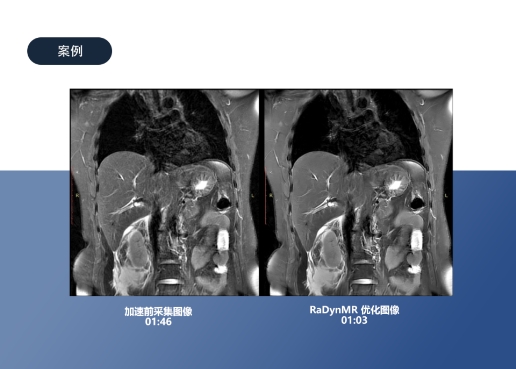

影动医疗已经与数十家顶尖医疗院校、医院及第三方影像中心开展前沿合作。截至目前,其自主研发的成像重建增强产品RaDynPET、RaDynMR、RaDynCT、RaDynSPECT覆盖面最为广泛,已在上海长海医院,北京大学附属第三医院等各大医院、体检中心展开临床应用。